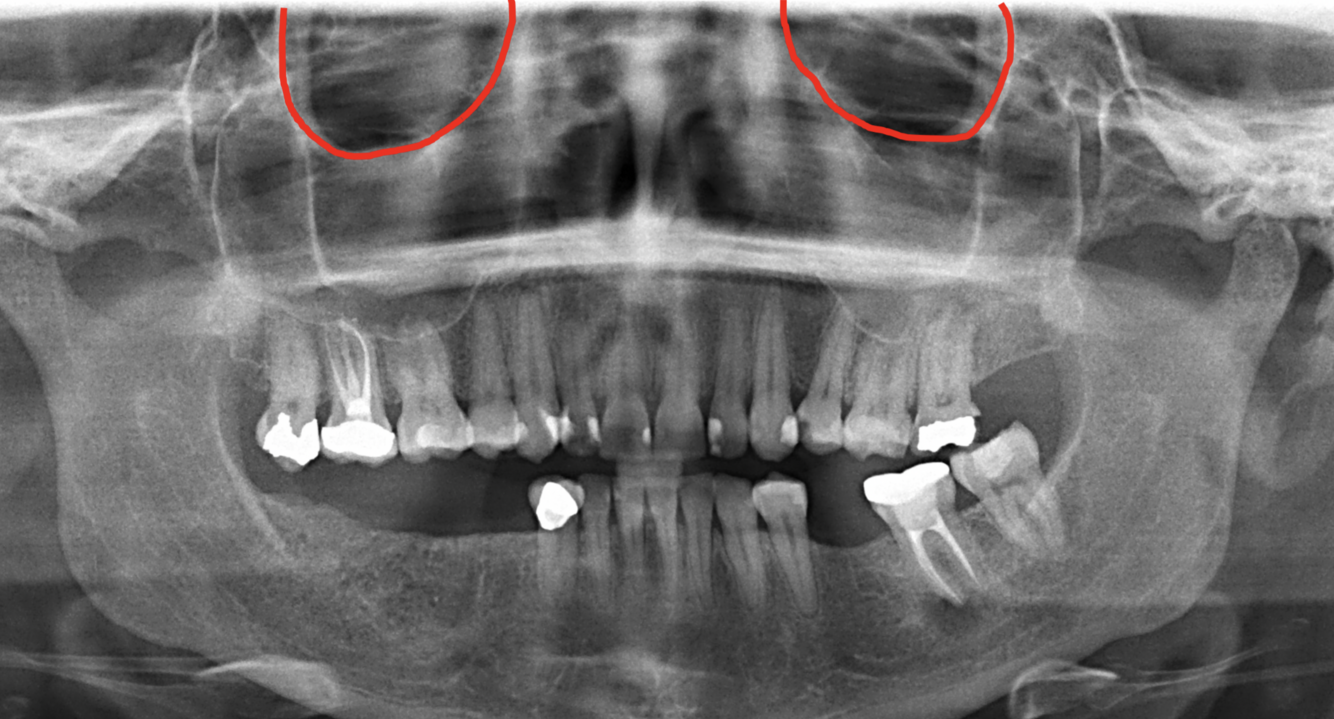

What does the red indicate in the following image?

Maxillary sinus